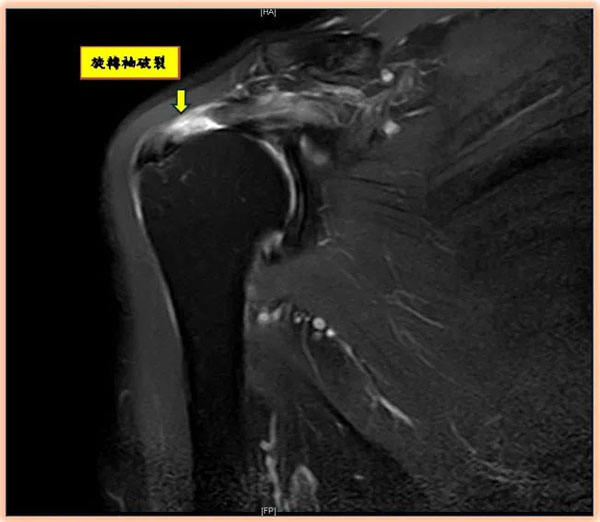

旋转肌袖破裂如何诊断?陈昱彰表示,起初常被误认为肌腱拉伤或五十肩,但症状久未改善时,应尽早请骨科医师进行正确诊断与治疗。诊断方式除理学检查、X光、超音波外,也常以核磁共振(MRI)确认破裂程度与型态,作为手术规划依据。